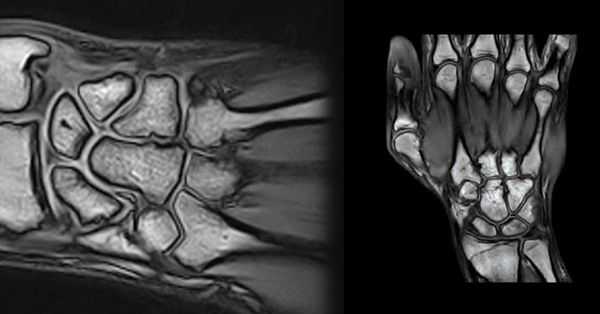

Первая из 20 последовательных Т1-взвешенных томограмм запястья в продольной проекции с направлением срезов от локтевой (медиальной) стороны к лучевой (латеральной). Сухожилие ЛоРЗ пересекает дистальный отдел локтевой кости в локтевой борозде ЛоРЗ. Мышца, отводящая мизинец—самая медиальная и передняя мышца гипотенара. Гороховидно-пястная связка соединяет гороховидную кость с V пястной костью. Она прилежит к гороховидно-крючковидной связке (следующая томограмма). Хорошо виден гороховидно-трехгранный суставной карман. Мышцы гипотенара менее прочные в области отхождения их от удерживателя сгибателей. Сухожилие локтевого сгибателя запястья прикрепляется к гороховидной кости. Локте-трехгранная связка отходит от ладонной лучелоктевой связки и прикрепляется к ладонной поверхности трехгранной кости. Локтевые нерв и артерия проходят в канале Гийона латеральнее и дистальнее гороховидной кости. Выступает крючок крючковидной кости. Треугольный хрящевой диск (ТХД) визуализируется в виде диска с низкоинтенсивным сигналом между головкой локтевой кости и трехгранной костью. Ладонная и тыльная лучелоктевые связки вместе с ТХД и прилежащими структурами образуют треугольный фиброзно-хрящевой комплекс. Внешние и внутренние связки иногда сложно выделить в качестве отдельных образований. Указатели направлены к визуализируемым связкам или месту возможного обнаружения связки. Тыльная межзапястная связка—основная связка, стабилизирующая тыльный отдел запястья, но визуализируется только на ограниченном участке. Сухожилия поверхностного и глубокого сгибателей пальцев проходят под горизонтально расположенным удерживателем сгибателей. Сухожилия разгибателя пальцев проходят через IV канал разгибателей и фиксируются удерживателем разгибателей. На ладонной поверхности можно увидеть пучки лучеладьевидно-локтевой и короткой лучеполулунной связок. На задней поверхности можно увидеть тыльную лучезапястную связку, отмечена область тыльной межзапястной связки. Характерный наклон в ладонную сторону дистального отдела лучевой кости обусловлен тем, что тыльный край лучевой кости расположен более дистально, чем ладонный (12°). Центральная ость запястья образована основанием III пястной кости, головчатой и полулунной костями, а также полулунной ямкой лучевой кости. Сухожилие разгибателя указательного пальца—самое латеральное сухожилие IV канала разгибателей. Сухожилие мышцы, противопоставляющей большой палец, на этом срезе отходит от удерживателя сгибателей. Срединный нерв расположен поверхностнее сухожилия длинного сгибателя большого пальца и глубже удерживателя сгибателей. Длинная лучеполулунная связка отходит от лучевой кости непосредственно латеральнее лучеладьевидной и короткой лучеполулунной связок. Сухожилие длинного разгибателя большого пальца лежит медиальнее бугорка Листера и в дистально-латеральном направлении на пути к большому пальцу пересекает сухожилия длинного и короткого лучевых разгибателей запястья. На этом срезе визуализируются сочленения трапециевидной, головчатой и ладьевидной костей между собой. Сухожилие длинного сгибателя большого пальца проходит под локтевым нервом непосредственно медиальнее сухожилия лучевого сгибателя запястья. Сухожилие короткого лучевого разгибателя запястья (КЛуРЗ) прикрепляется к основанию III пястной кости. Сухожилие лучевого сгибателя запястья проходит поверхностнее бугорка ладьевидной кости и прикрепляется к основанию II пястной кости. Лучеладьевидно-головчатая связка отходит от края ладонной поверхности лучевой кости. Сухожилие лучевого сгибателя запястья проходит поверхностнее бугорка ладьевидной кости и прикрепляется к основанию II пястной кости. Сухожилие короткого лучевого разгибателя запястья (КЛуРЗ) пересекает тыл запястья и прикрепляется к тыльной стороне основания III пястной кости. Наиболее латеральный отдел лучеладьевидно-головчатой связки иногда называют лучевой коллатеральной связкой. Сухожилие длинного лучевого разгибателя запястья (ДЛуРЗ) пересекает тыл запястья и прикрепляется к основанию II пястной кости. Лучевая артерия, поверхностная ветвь лучевого нерва и латеральная подкожная вена руки проходят через анатомическую табакерку, ограниченную костью-трапецией, ладьевидной костью и шиловидным отростком лучевой кости. Сухожилия длинной мышцы, отводящей большой палец и короткого разгибателя большого пальца, образуют ладонный край анатомической табакерки, а сухожилие длинного разгибателя большого пальца формирует ее тыльный край. Сухожилия длинной мышцы, отводящей большой палец и короткого разгибателя большого пальца, образуют дистальный край анатомической табакерки после соединения непосредственно дистальнее I запястно-пястного сустава. Лучевая артерия разветвляется и продолжается в дистальном направлении, образуя глубокую ладонную дугу. Сухожилия длинной мышцы, отводящей большой палец и короткого разгибателя большого пальца соединяются в месте прикрепления к основанию I пястной кости.

Снимки, полученные с помощью МРТ — это серия срезов толщиной от 1 мм, сделанная через область обследования в нескольких плоскостях. На них четко видны кости, образующие лучезапястный сустав, суставная полость и суставной хрящ, оболочка сочленения, связки, мышцы и их сухожилия.

При расшифровке снимков врач обращает внимание на ширину суставной щели, состояние хряща и суставной оболочки, целостность связочного аппарата. При наличии объемных образований МРТ позволяет с высокой точностью определить, что это — киста или опухоль. Изучая динамику накопления контраста, можно выявить ранние признаки воспаления или злокачественного процесса.